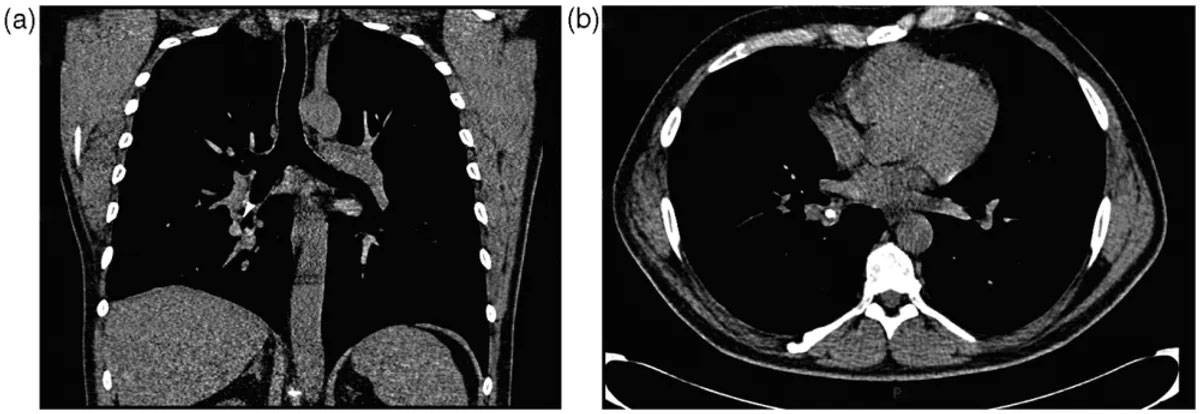

وأظهرت صور التصوير المقطعي المحوسب وجود كتلة غير واضحة في الجزء السفلي الأيمن من الرئة. في البداية، لم يكن الأطباء متأكدين مما إذا كانت كتلة مرضية أو تراكما متكلسا للإفرازات، لكن شكلها بدا غريبا على نحو لافت. فقد لاحظ الفريق الطبي أنها تبدو كجسم صلب يشبه إلى حد كبير "مخروطًا مروريا صغيرا للعب الأطفال".